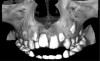

Fig 1. A 0.2-mm thick sagittal image at the level of the upper left central incisor (tooth No. 9) of a 7-year-old boy who presented with a mesodont. Movement artifacts were present as evidenced by double contours and an overall blurring of the image.

Figure 1

Fig 2. Frontal shaded surface rendering of the same patient shown in Fig 1. The threshold of the image has not been adjusted from the default value to allow for comparison.

Figure 2